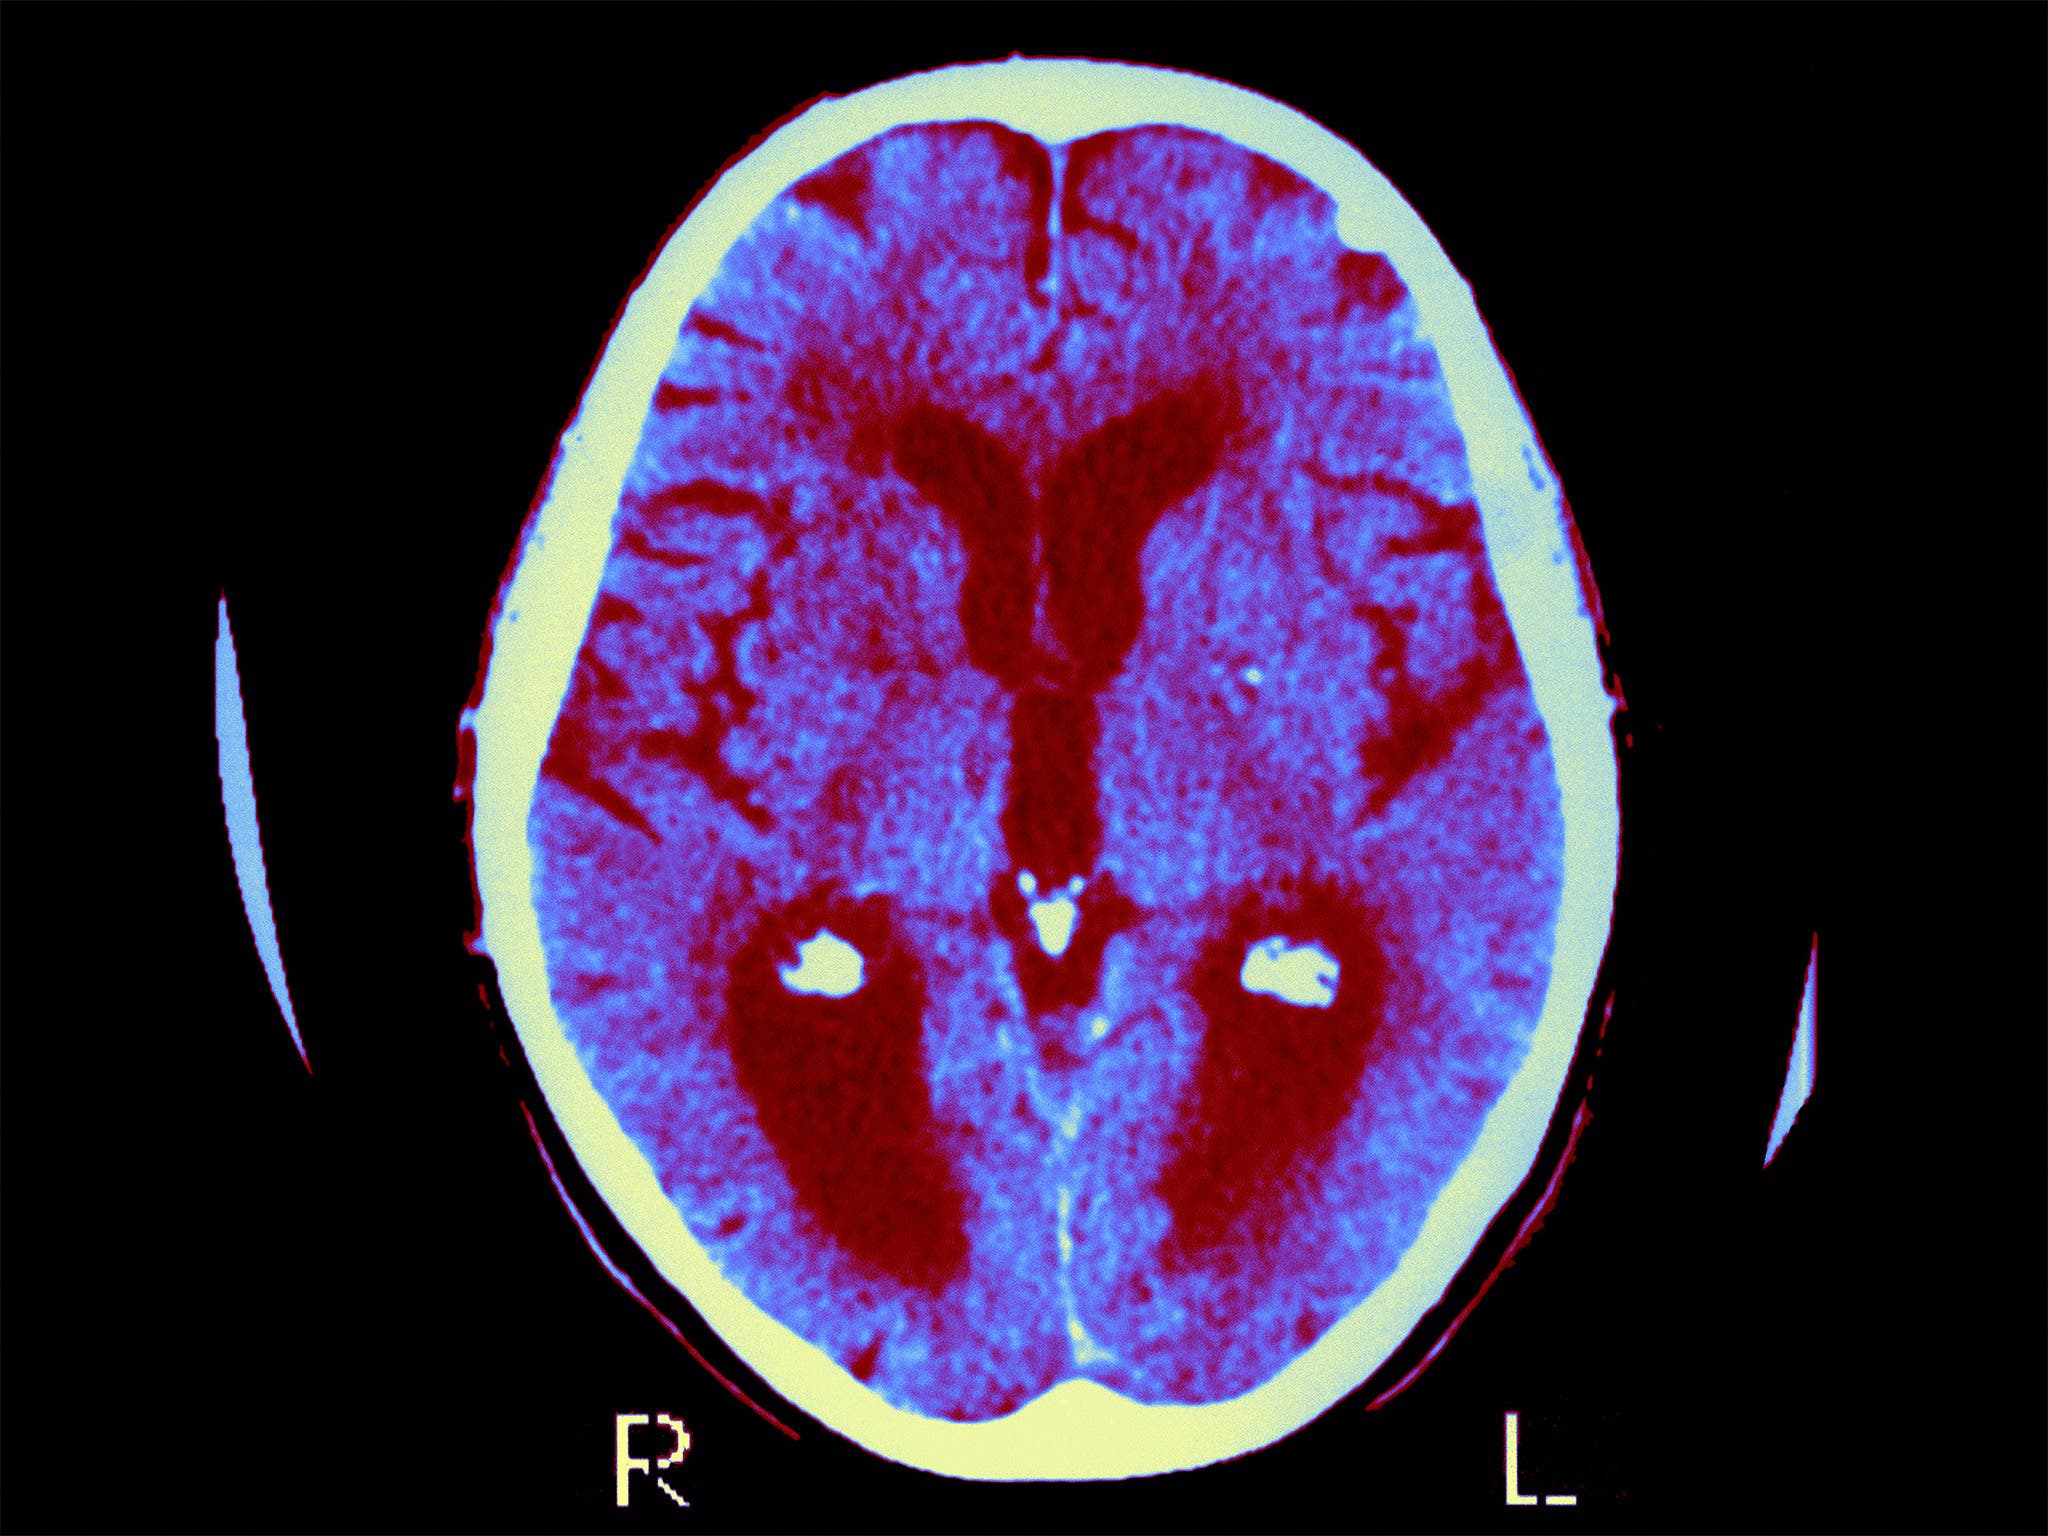

Что такое энцефалит расмуссена - фото презентация